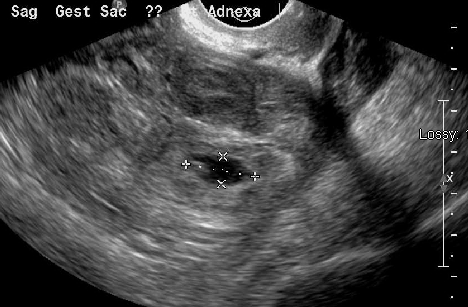

초음파 검사는 자궁외 임신 진단의 핵심적인 방법이다. 특히 질식 초음파 검사는 나팔관 내에 임신낭이 있고 태아 심장이 보이는 경우 자궁외 임신 진단에 매우 높은 특이성을 보인다. 이 검사는 질 내에 변환기를 삽입하여 진행하며[32], 자궁외 임신에 대해 최소 90%의 민감도를 가진다.[5]진단적 초음파 소견은 다음과 같다:

- 가성낭: 양성 임신 검사 결과에도 불구하고 자궁 내 임신이 아닌 액체 덩어리인 가성낭이 최대 20%의 여성에게서 나타날 수 있어 자궁외 임신 가능성을 배제할 수 없다.[5]

4. 2. 임신 위치 불명 (PUL)

임신 위치 불명(Pregnancy of Unknown Location, PUL)은 임신 반응 검사에서는 양성이지만, 질식 초음파 검사를 통해서는 자궁 내 또는 자궁 외 임신을 확인할 수 없는 상태를 말한다.[5] 초기 임신 전문 부서에서 초음파 검사를 받는 여성의 약 8%에서 10%가 PUL로 분류될 수 있다.[5] PUL의 실제 상태는 진행 중인 정상적인 자궁내임신(IUP), 유산된 임신, 자궁외임신, 또는 드물게 지속 PUL(Persistent PUL)일 수 있다.[5]

초음파 검사에서 자궁내임신(IUP)이 보이지 않을 때, 사람융모성 생식선자극호르몬(β-hCG) 수치 측정이 진단에 도움을 줄 수 있다. 낮은 β-hCG 수치는 임신이 자궁 내에 있지만 초음파로 보기에 너무 작다는 것을 의미할 수 있다. 일부에서는 β-hCG 수치가 약 1500 mIU/mL 이상일 때 질식 초음파 검사에서 자궁내임신이 보여야 한다고 보지만, 자궁외임신을 확진하는 단일 β-hCG 역치는 없으며, 고해상도 질식 초음파 검사가 가장 중요한 진단 도구이다.[3] 질식 초음파 검사에서 자궁내임신이 없으면서 부속기(난소, 난관 등)에 종괴가 보이면 자궁외임신 가능성이 크게 높아진다(LR+ 111). 반대로 부속기 이상이 없으면 자궁외임신 가능성은 낮아진다(LR- 0.12).[3] β-hCG 수치가 1500 mIU/mL 이상인데도 자궁이 비어있는 것으로 보이면 자궁외임신의 증거일 수 있지만, 매우 작은 자궁내임신일 가능성도 배제할 수 없다.[3]